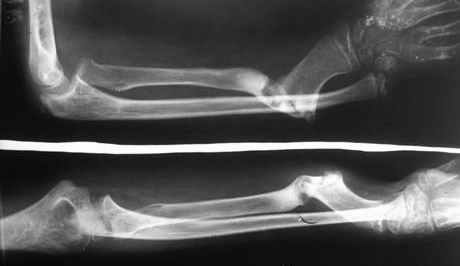

Глубокоуважаемые коллеги!Из ЦРБ поступил больной с застарелым переломом Галеацци. 3 года тому назад оперирован по месту жительству - открытый остеосинтез лучевой кости, вывих не устранен. Хотелось бы узнать Ваше мнение по поводу тактики хирургического лечения. Каримов Муродулла Юлдашевич кандидат медицинских наук, доцент заведующий кафедрой травматологии и ортопедии,ВПХ с нейрохирургией Ташкентская Медицинская Академия

Трудно говорить, не видя первичных снимков, но по представленным - мнение за повреждение Галeацwи не складывается...

Тем более, что судя по снимкам это ребенок, а в этой возрастной группе данное травматическое состояние крайне редко...

По моему предположению, здесь был обычный разгибательный перелом на гр. с-в\3 диафиза луча в сочетании со смещением в лучевую сторону. По той или иной причине (вам виднее) возник ложный сустав в том же (или близком к тому) положении...

В настоящее время на фоне ложного сустава имеется угловая деформация, препятствующая ротационным движениям в предплечье, с лучевой девиацией кисти и косметическими (помимо функциональных) проблемами...

На фоне всего этого (продольное относительное "укорочение" луча) имеется и рентнгенологически видимый продольный подвивих (проксимальный) в дистальный радиоульнарном сочленении... Но это не

Галеацци...

??? Головка, судя по снимкам, не в вывихе.

Головка лучевой кости на месте. Функция локтевого сустава также в полном объеме.